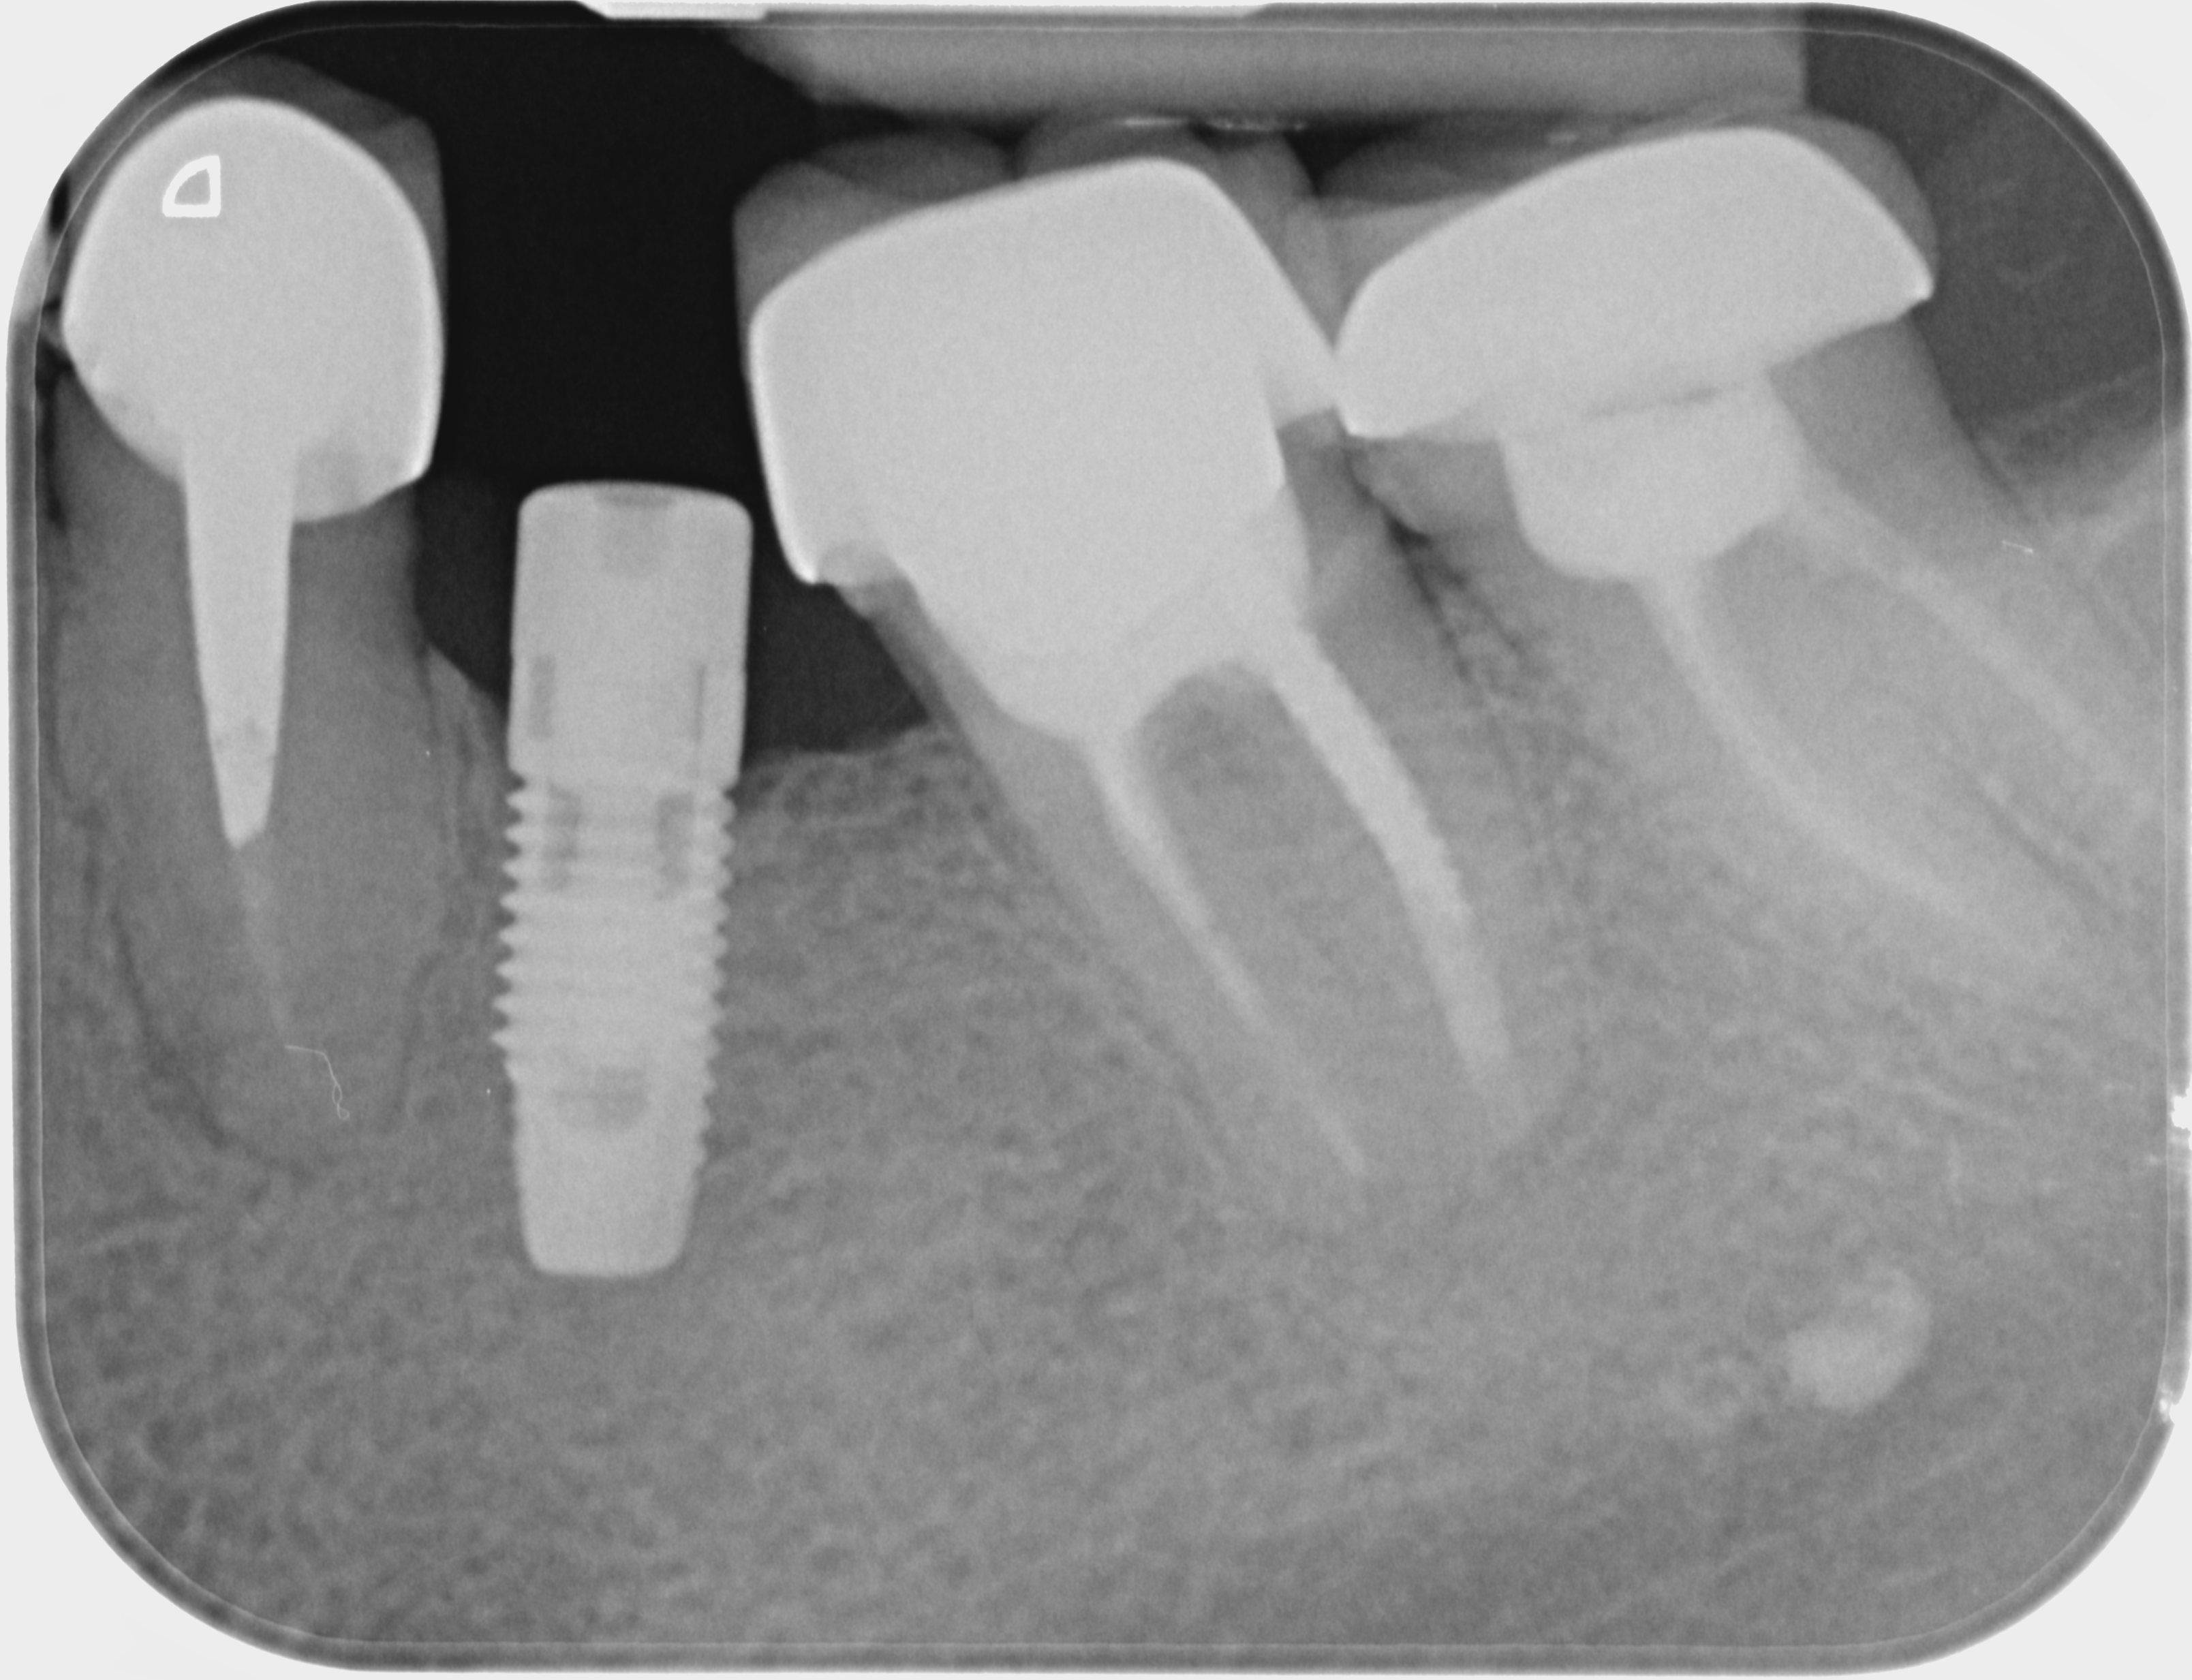

Pouvez vous me dire quel est la marque de cet implant ! Merci

Nobel Replace